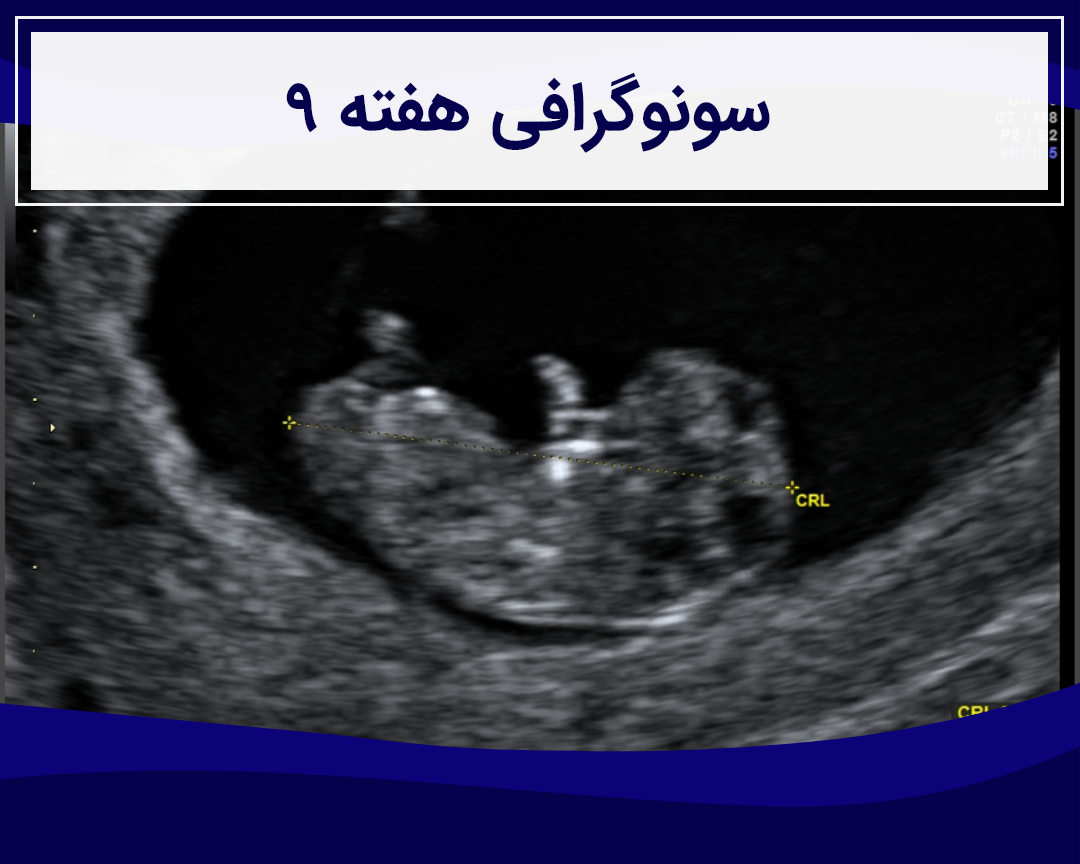

در هفته ۱۰ , وزن رویان در حدود ۴ گرم می باشد و CRL او نیز در حدود ۳.۱ سانتی متر اندازه گیری می شود. سونوگرافی نحوه رشد رویان را به طور واضح مشخص خواهد کرد. همچنین پزشک می تواند بر اساس این اندازه گیری ها سن بارداری را محاسبه کند و تاریخ زایمان را پیش بینی کند.